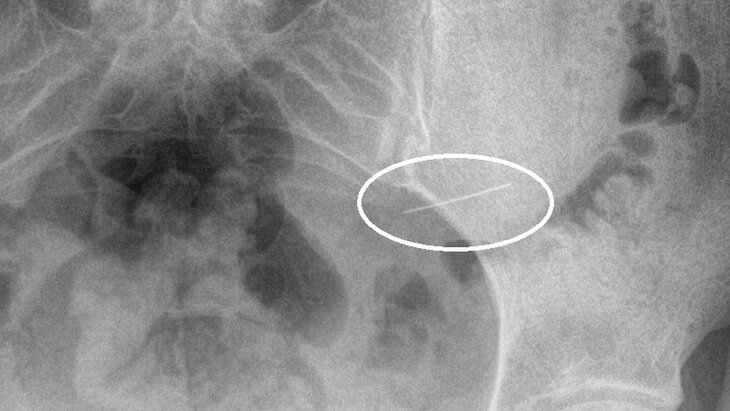

Специалисты Красногорской больницы оказали помощь девушке, поступившей в медучреждение из-за случайно проглоченной швейной иглы. Об этом заявили в пресс-службе Минздрава Подмосковья.

По итогам рентгенологического исследования врачи обнаружили, что инородное тело находилось в желудке. Пациентку направили на срочное хирургическое вмешательство.